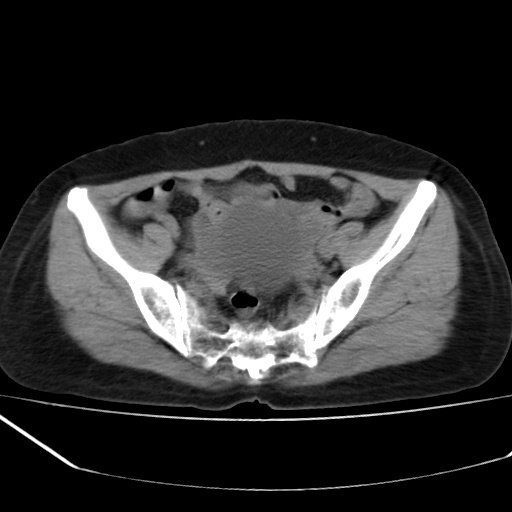

病人不肯增强,是不是膀胱右前方那一个

盆腔右前壁囊性占位,右耻骨轻微骨质吸收.性质选定,建议增扫或病理!!!!!

我只好报盆腔右前壁囊性占位,性质选定,建议增扫或病理.

膀胱右前方占位

病史?临床表现?膀胱右前方囊性占位,边缘光整,考虑良性,建议结合b超检查,既然要做手术,等手术结果吧,只是觉得手术仓促了些。

膀胱右前壁囊性占位,性质难定,要做手术,那就等手术结果吧.